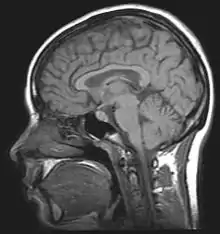

MRI

MRI of the human brain.